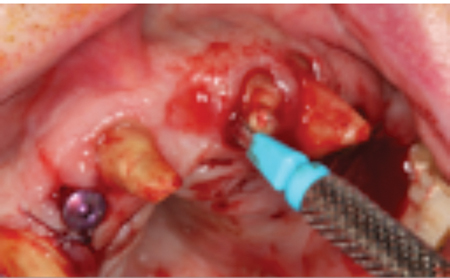

This article describes the treatment planning steps involved in creating a dental implant solution for a case of a failing dentition, making use of hopeless teeth and tooth roots) to serve as temporary abutments for a fixed-provisional prosthesis, while maintaining as much of the natural dentition as possible. The goal was to provide chewing efficiency and patient comfort during the osseointegration healing period while simultaneously preventing premature loading of newly placed dental implants as the patient is transitioned to the final definitive prostheses.

In this article we will highlight the reverse strategy of using ‘hopeless teeth and/or tooth roots to help safeguard newly placed dental implants’ from premature loading during the osseointegration period by serving as temporary abutments for fixed-partial temporary prostheses. These provisional prostheses can accept occlusal load while facilitating a smooth transition to final prosthesis. As such, the ‘rush to finish’ becomes less of a factor.

This was necessary to manage traumatic horizontal root fracture #21.

- Extraction of #16, 12, 22 and 26. (Socket grafting #16, and 26 to preserve existing bone volume).

- Immediate implant placement in sites #12, 22, 14 and 24.